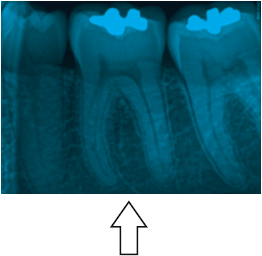

Analise a figura abaixo e assinale a alternativa correta:

Figura. Radiografia periapical